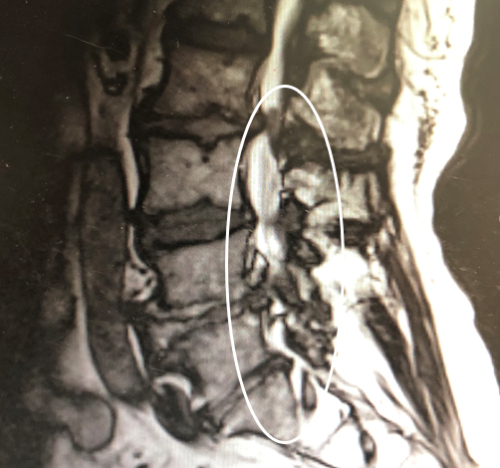

近日,年近八旬的鞏爺爺病情已經(jīng)到了不用拐杖很難正常行走的地步。在孫子的勸說(shuō)下,他來(lái)到南京腦科醫(yī)院就診。我院脊柱脊髓多學(xué)科MDT團(tuán)隊(duì)許利剛主任和耿良元醫(yī)生對(duì)其聯(lián)合會(huì)診,并進(jìn)行了詳細(xì)的檢查。據(jù)耿醫(yī)生介紹,鞏爺爺?shù)难礐T和磁共振顯示其腰椎多節(jié)段狹窄,壓迫了神經(jīng)根,從而導(dǎo)致了腿部的一系列癥狀。

術(shù)前CT\MR顯示鞏爺爺L3/4 L2/3椎管狹窄